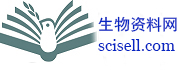

油红O染色(Oil Red O Stain)

油红O染色可用于脂肪细胞和中性脂肪的组织学染色。

脂肪细胞:红色

中性脂肪:红色

细胞核:蓝色

图 1. 油红O染色 Oil Red O Stain